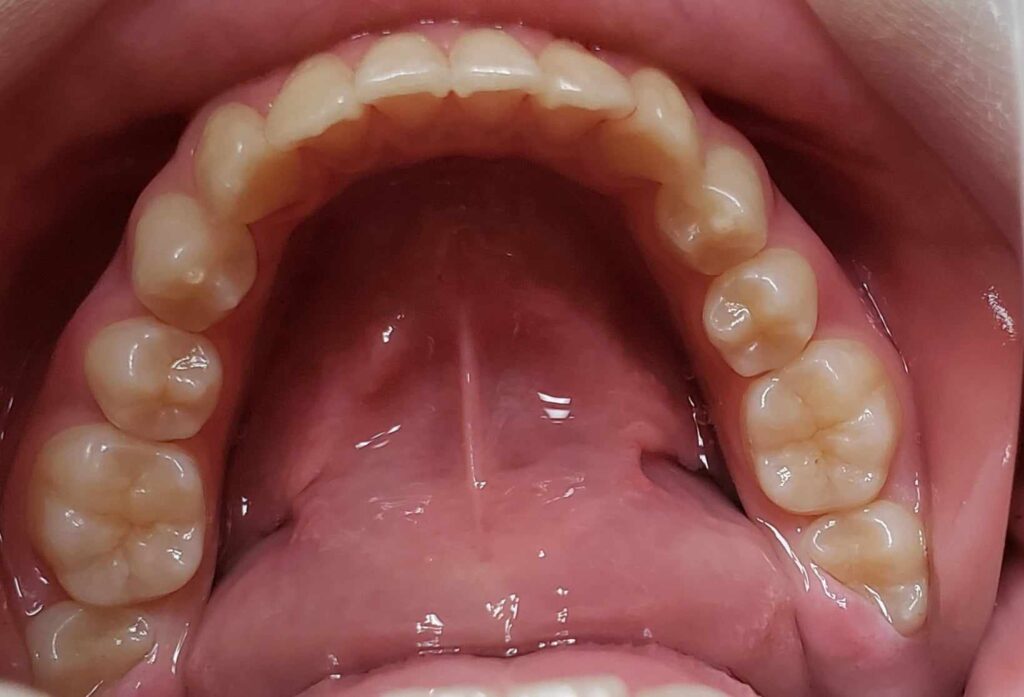

治療3年後

下顎前歯叢生予防のため、高校1年になり、左右下埋伏の親知らずの抜歯を行いました。本人歯並びが良くなって、ホワイトニングも希望されましたので、行うことになりました。かなり白くなりました。個人的にこれが本当の人工物に頼らない理想的な治療方法(矯正+ホワイトニング)だと思ってます。これをもって、私の治療責任は果たされ、治療終了となります。恐らくこの子は、今のままの予防概念であれば、今後歯のトラブルに遭遇する確率は低いと考えられます。